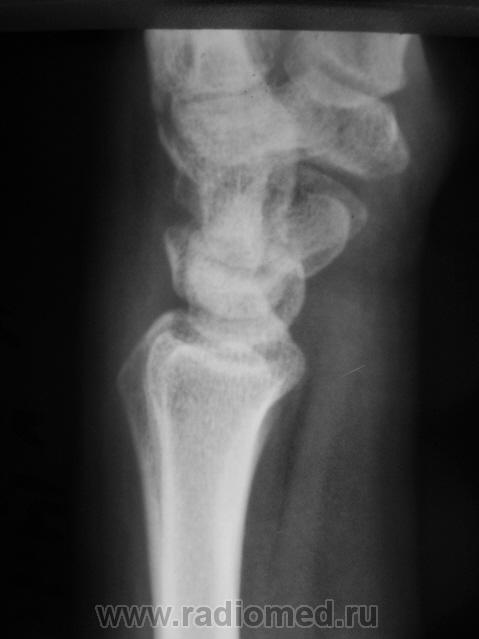

Катенёв Валенти... Дата публикации 15.10.2009, 20:32 Травма неделю тому. Пациент направлен на рентгенологическое исследование лучезапястного сустава с диагнозом "Перелом". Произведено исследование. Ваше мнение коллеги? Чт, 15/10/2009 - 20:36 #1 В.Б. Серов Не на сайте Был на сайте: 3 недели 3 дня назад Зарегистрирован: 16.07.2008 - 10:15 Публикации: 1376 Нужен косой снимок, подтвердить/опровергнуть перелом ладьи. Зри в корень! Чт, 15/10/2009 - 21:37 #2 Наталия Не на сайте Был на сайте: 9 лет 2 недели назад Зарегистрирован: 30.07.2008 - 13:24 Публикации: 538 Перелом ладьевидной кости без смещения виден хорошо. Чт, 15/10/2009 - 21:53 #3 Катенёв Валенти... Не на сайте Был на сайте: 7 лет 5 месяцев назад Зарегистрирован: 22.03.2008 - 22:15 Публикации: 54876 Да. линия перелома в ладьевидной кости, весьма хорошо дифференцируется

Перелом ладьевидной кости без смещения виден хорошо.

Да. линия перелома в ладьевидной кости, весьма хорошо дифференцируется